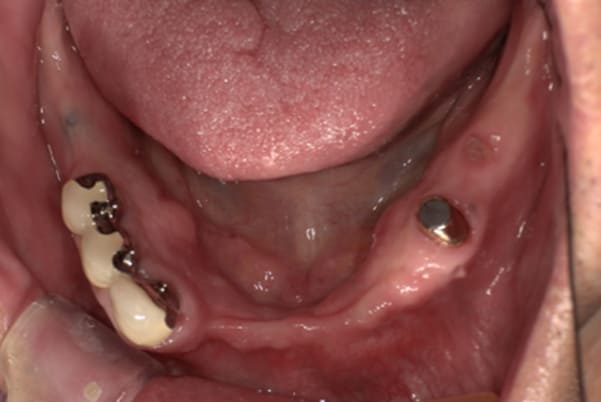

症例レポート[CASE.04]

前歯がとれて痛い、

食事もできず、見た目も悪い

- 女性(60代)

- 前歯がとれて、痛い、食事ができない、見た目が悪く人に会えないので何とかしてほしい

- 上顎精密金属総入れ歯

- 下顎精密金属部分入れ歯

- 磁性アタッチメント(白金加金) 1歯

上前歯はブリッジの差し歯により根が折れ炎症を起こしお痛みのある状態でした。

原因は長期使用により下の義歯の歯が削れたことにより、下前歯が上前歯を突き上げ強い力が加わっていたことが根本的な原因と考えられます。

治療前は、奥歯が下がり、かみ合わせが乱れています。適切な入れ歯はそのままのかみ合わせで義歯を作るのではなく治療後のように、前歯から奥歯までのラインが真っすぐ揃った、かみ合わせの面を適切に付与し、よく咬め、残りの歯に負担がかからないかみ合わせとしました。

上顎治療前

根のみの7本は虫歯にもなっており歯肉は腫れあがっています。

残りの歯もレントゲンで重度の歯周炎によりぐらぐらな状態でした。